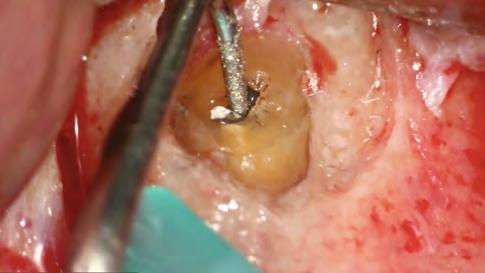

Después del retratamiento endodóntico convencional, el paciente fue sometido a una microcirugía apical. La osteotomía y la apicectomía se realizaron con el uso de una punta ultrasónica (W1CVDentus-Brasil). El fragmento apical del cono de plata se hizo visible en una ampliación de 12,5x (Figura 6). A fin de remover el fragmento apical, se utilizó una punta de ultrasonido P1M (Helse Ultrasonic - Brasil) (Figura 7, Figura 8). Después de la remoción microquirúrgica

del cono de plata, la preparación retrógrada fue realizada con la misma punta ultrasónica (Figura 9).

Figura 6 - Tercio apical después de apicectomía

ambientes húmedos, inducción y conducción en la formación de tejidos duros, cementogénesis con consecuente formación de adherencia periodontal normal, hacen el material más adecuado para estas situaciones clínicas. En este caso, se utilizaron nuevos materiales biocerámicos para obturación de la cavidad retrógrada. En primer lugar, el BIO-C® REPAIR (Angelus - Brasil) se utilizó para obturar el espacio en el conducto radicular. Un tapón apical de BIO-C® REPAIR (Angelus - Brasil) fue colocado sobre la raíz, sellando la retro cavidad (Figura 10, Figura 11).